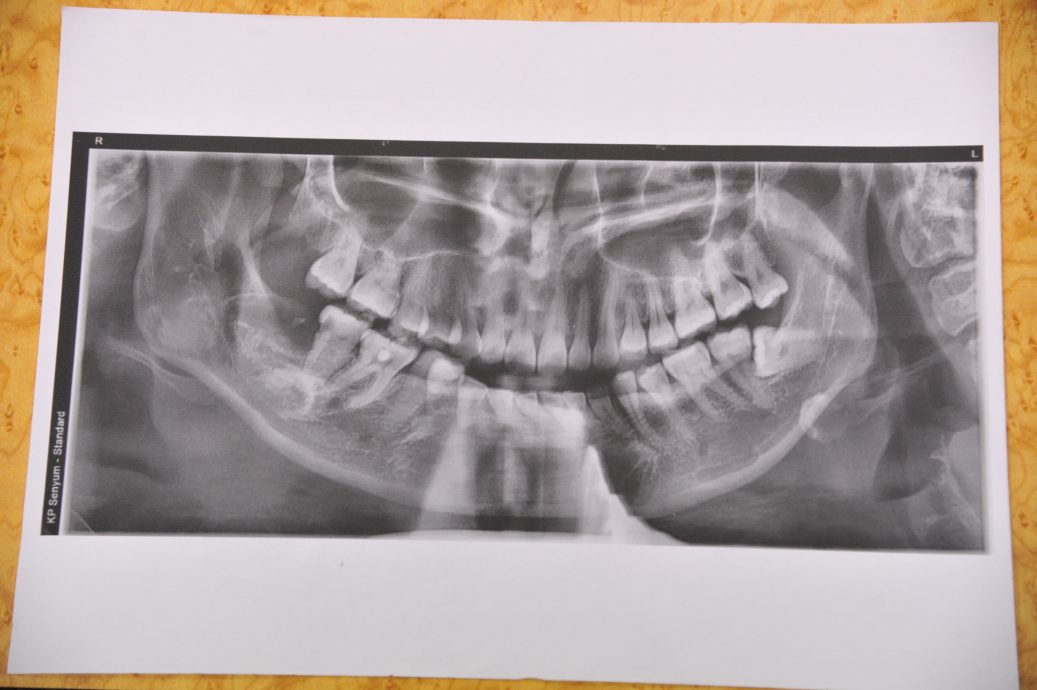

她指出在手术后的数天,她出现了下颚内缩、无法完全咬合、颈部无法扭动、眼皮震颤及胸口郁闷等后遗症,经到其他牙医诊所照X光片后,发现早前下颚的拔牙伤口处内留有碎齿,而颚部关节亦受损,且相信殃及后脊椎部位的神经线。”